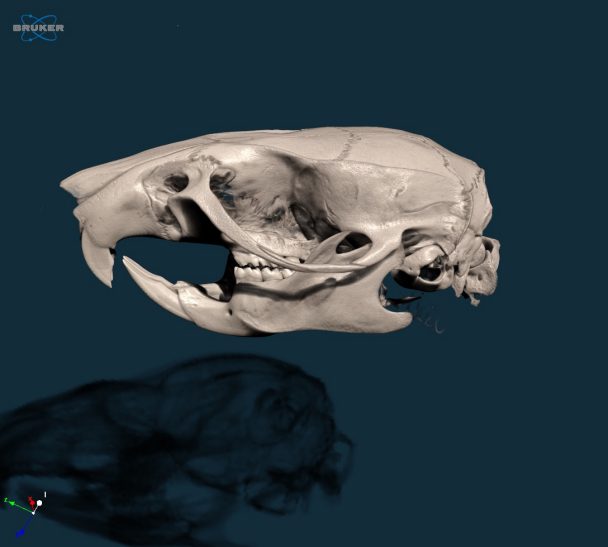

大鼠头骨的3D模型